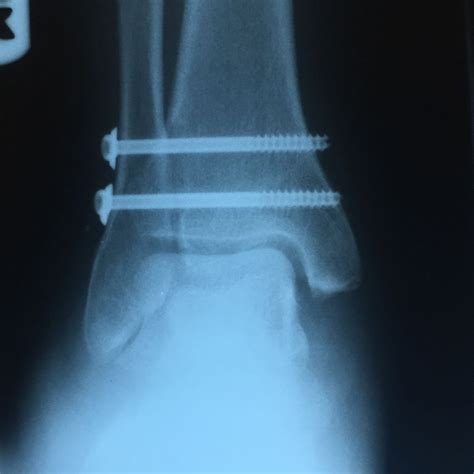

Diagnosing a high ankle sprain typically involves a physical examination and imaging tests. During the physical exam, a healthcare provider will assess the range of motion, stability, and tenderness of the ankle. Imaging tests, such as X-rays or MRI scans, may be ordered to confirm the diagnosis and rule out other potential injuries, such as fractures.

In some cases, a stress test may be performed to evaluate the stability of the syndesmotic ligaments. This test involves applying pressure to the ankle to see if there is any excessive movement or instability.

• Surgery in severe cases to repair damaged ligaments